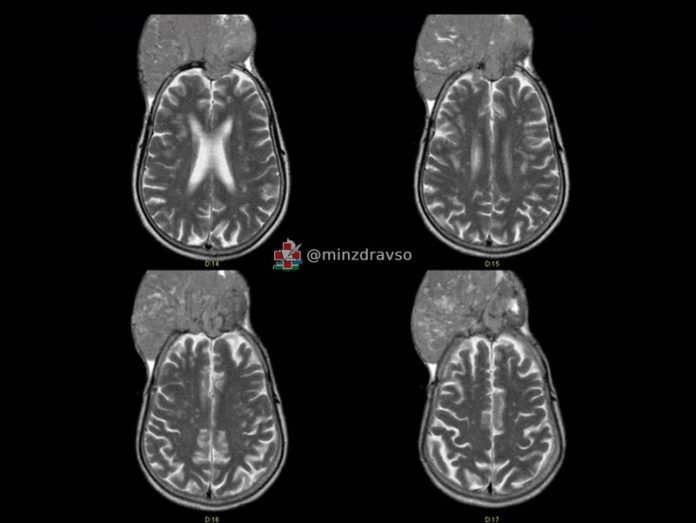

Спасение от гигантской опухоли: история уникальной операции

Новости Саранска и Республика Мордовия t353 В Свердловской области врачи онкодиспансера провели сложную операцию по спасению жителя Краснотурьинска. У мужчины обнаружили огромную менингиому, которая начала разрушать кости черепа и вышла за его пределы на 10 см. Портал новостей Саранска и Республика Мордовия eaj2 По словам нейрохирурга Павла Гвоздева, пациент долгое время не обращался за помощью, несмотря на стремительный рост опухоли, достигшей размеров 15×15 см. Хотя новообразование было доброкачественным, оно угрожало потерей слуха, зрения и других жизненно важных функций. Операция длилась 7 часов: врачи перекрыли сосуды, удалили опухоль, установили титановую сетку и восстановили форму черепа. Также хирурги провели пластику кожи, чтобы сохранить возможность носить прическу. Процедура завершилась успешно.